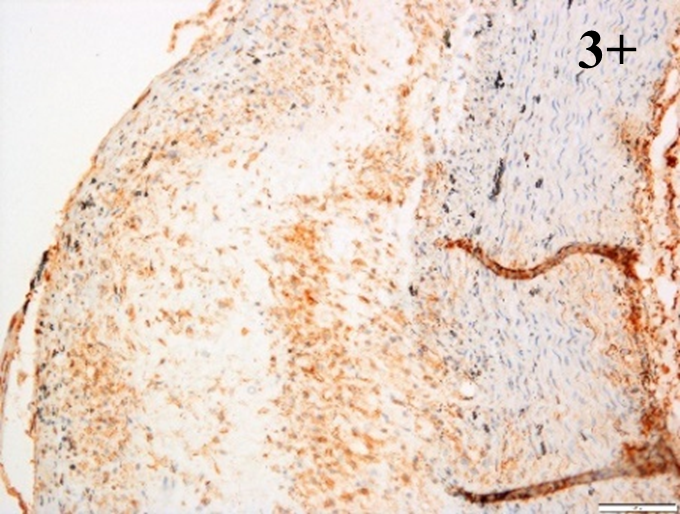

According to the percentage endothelial staining of cells, semi-quantitative

scores were applied. Score: 0 (negative); 1+ (1–10% positive cells); 2+

(11–25% positive cells) and 3+ (

Medium to high expressions of adhesion molecules, such as ICAM-1, VCAM-1 and

e-selectin were observed in the aortas of rabbits fed with HCD. This represents

the initiation of the lesion stage, where the endothelial cells have been

stimulated by the ox-LDL to express the adhesion molecules, which could lead to

the recruitment of monocytes and transmigrate into the intima by diapedesis as

well as differentiate into pro-atherogenic macrophages [47]. An increased

expression of pro-inflammatory biomarkers, such as IL-6, IL-8 and NF-